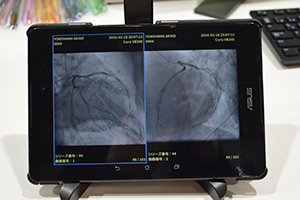

●Android OS対応DICOM画像ビューワのプロトタイプを紹介

GoodnetのDICOM画像ビューワ「GoodView」は,血管造影画像や超音波画像などのDICOMデータだけでなく,IVUSの長軸画像の比較表示・簡易計測,フォーマット変換機能が搭載された多機能ビューワ。それぞれの機能は,直感的な操作で使用でき,医療現場から集まるユーザーからの声を集約させ,アップデートが図られている。

動画の再生・停止・画像送り・ズームという診断時に必要な動作の多くをマウスのみで行え,動画像の閲覧作業を中断することなく,より直感的な操作と無駄の少ない画像参照が可能になる。